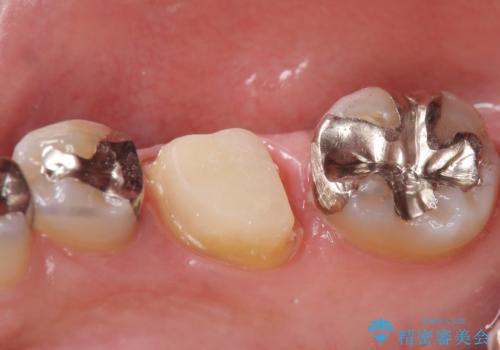

- 他院にて根尖病変があるため根管治療を勧められ当院にいらっしゃった方の症例です。

再根管治療を行い病変の縮小傾向を確認後、オールセラミッククラウンによる補綴を行いました。